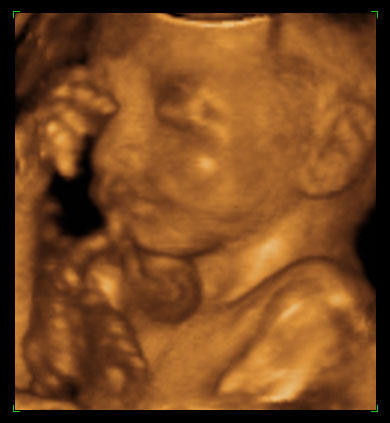

ултразвучни приказ бебе 24. недеље трудноће (1)